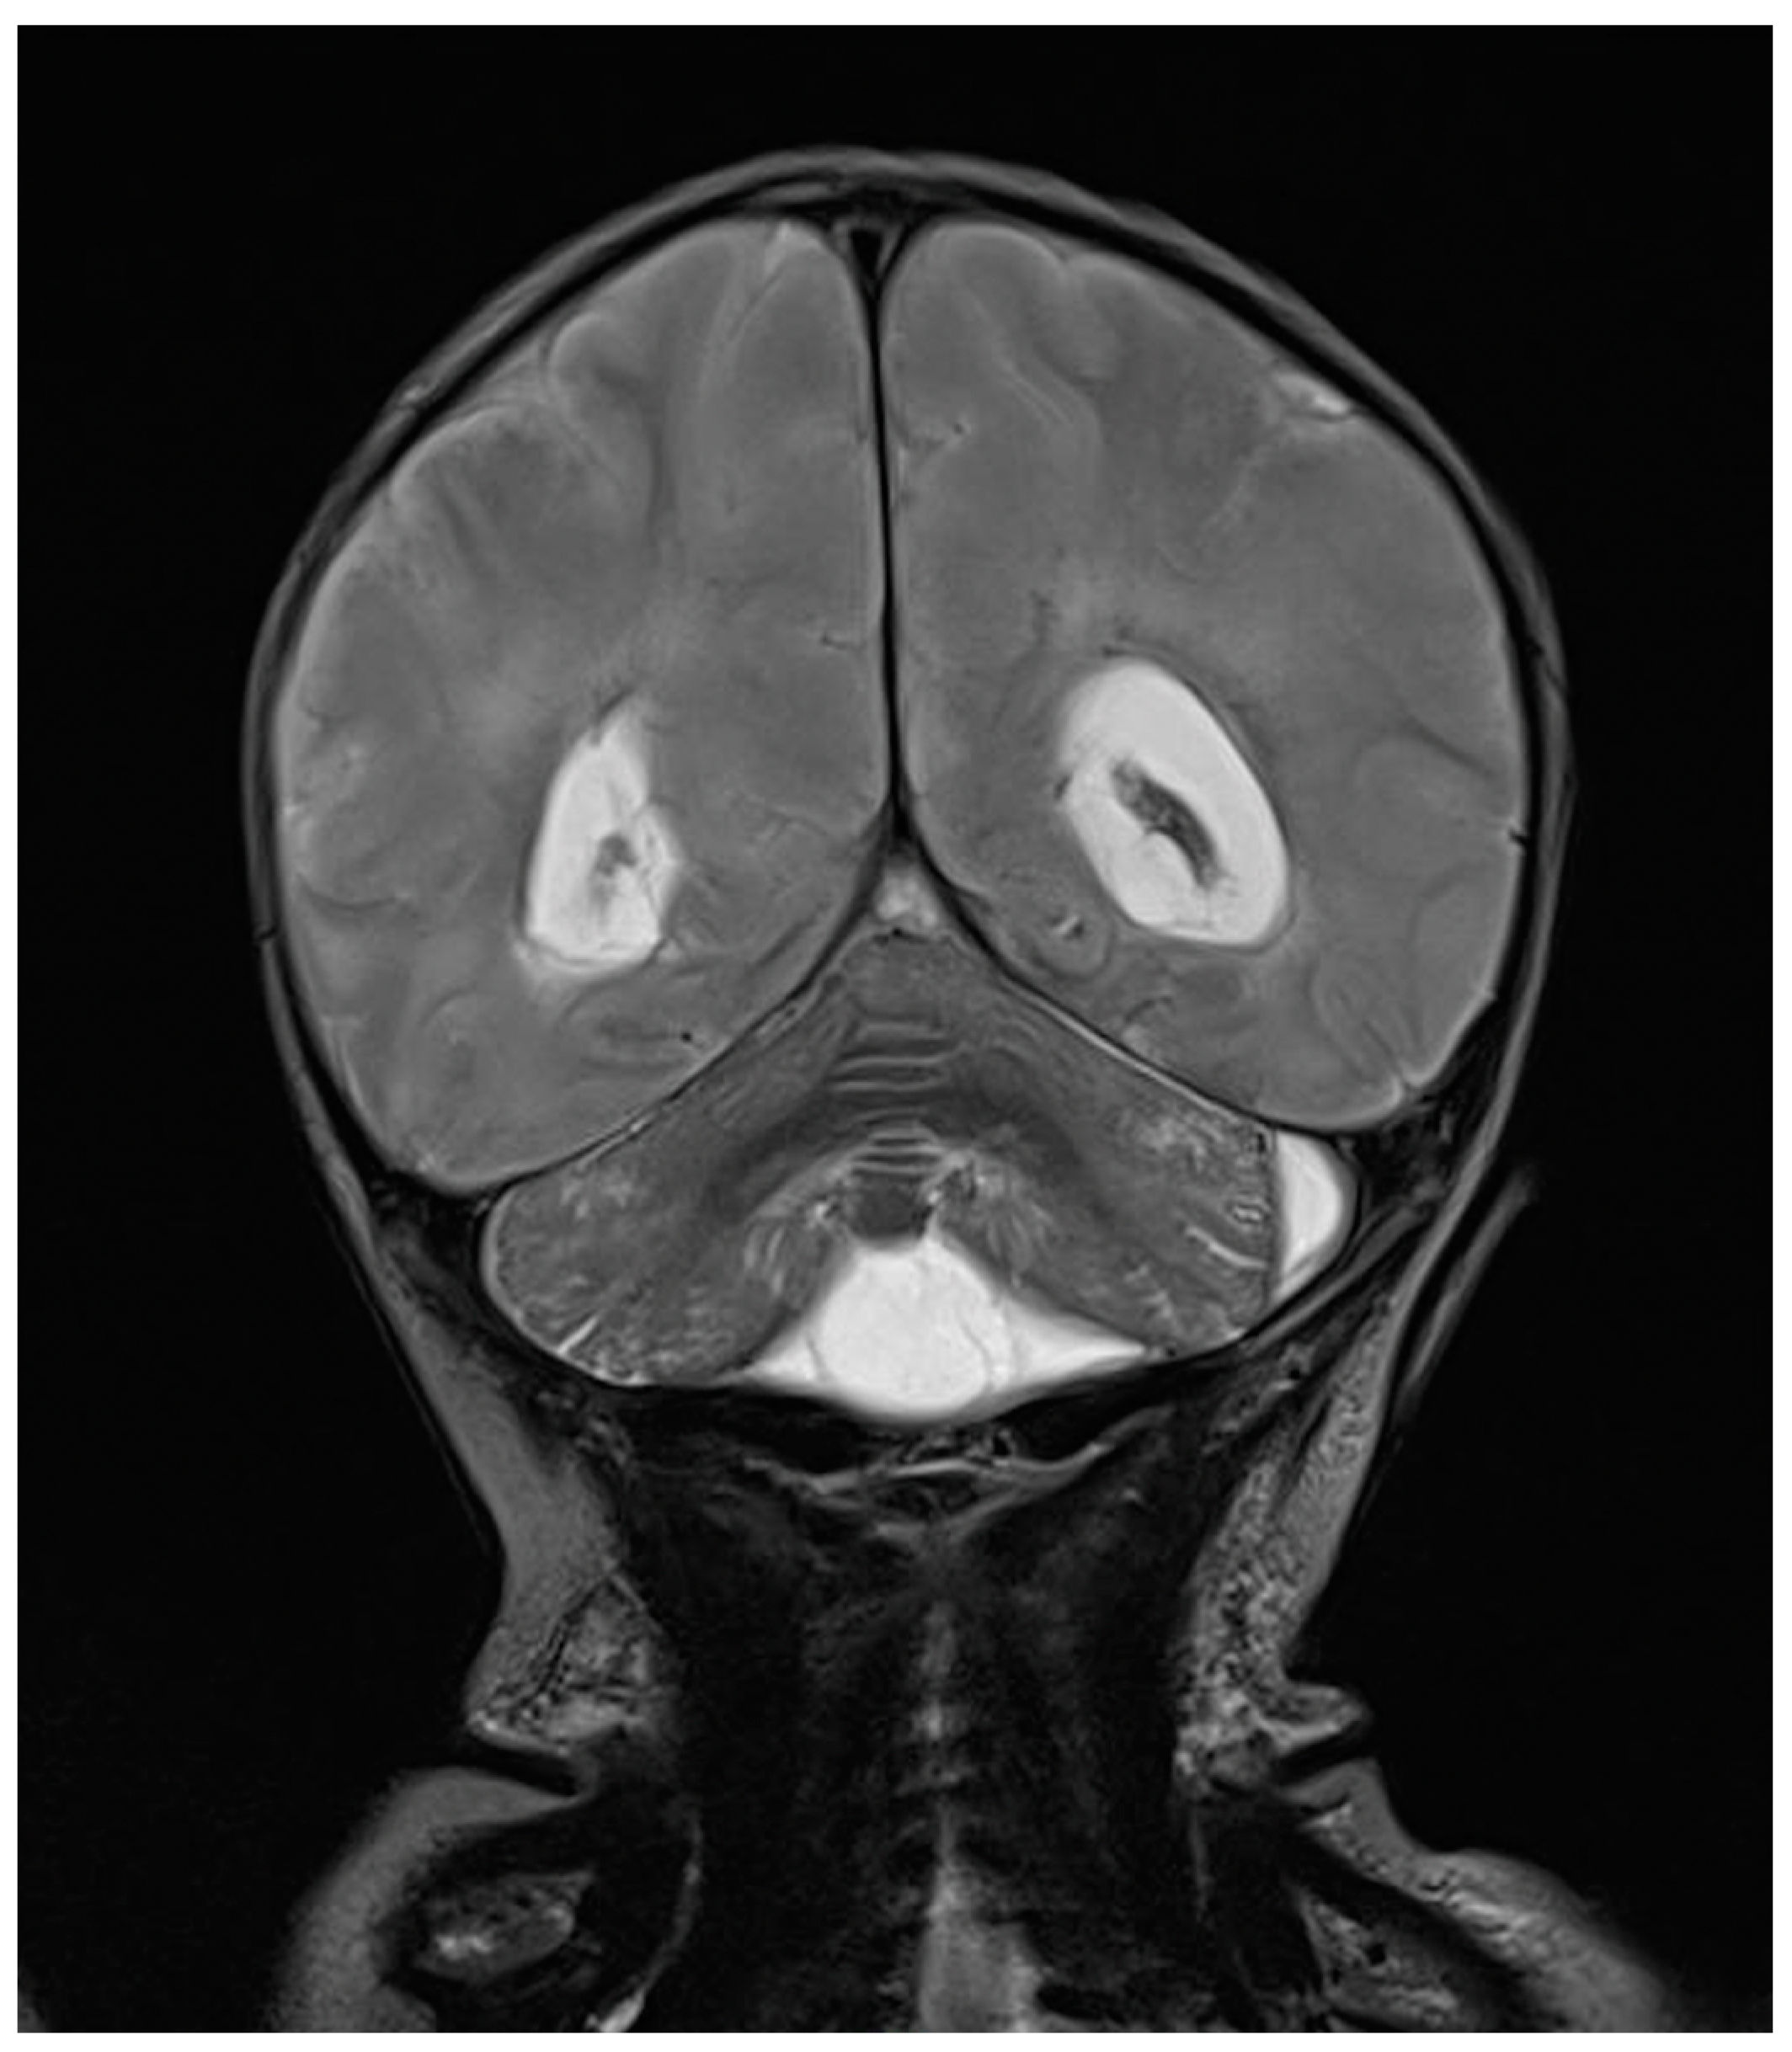

One day after the start of antibiotic therapy, the patient’s condition worsened, with subsequent epileptic seizures and episodes of bradycardia and apnea with desaturation, prompting the initiation of antiepileptic therapy, endotracheal intubation, and invasive mechanical ventilation. In the following days, further deterioration was observed, with progressive cerebral hypoperfusion and ventricular dilation noted on the trans-fontanelle ultrasound. The MRI showed findings consistent with meningoencephalitis with associated hypoxic injury, as well as sub- and supratentorial empyema (Figure 6). The patient was evaluated by neurosurgery without indications for intervention. The neonate died at 10 days of life. The infectious history and antibiotic therapy are schematized in the timeline in Figure 7.

Figure 6. Brain MRI in T2 sequence: picture compatible with meningoencephalitis associated with hypoxic suffering. Infratentorial empyema with small amounts of pus in ventricles supratentorially. Enlargement of lateral ventricles.